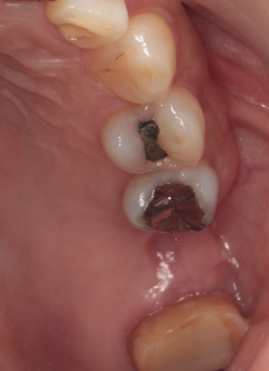

通常抜歯後、顎の骨は吸収する。後のインプラント治療が不利になる。抜歯前の疾患により歯を支える骨を失っており、即時埋入が難しい場合に行っている。

39歳男性